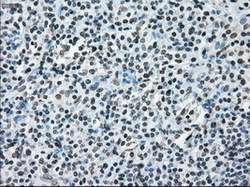

- Immunohistochemical staining of paraffin-embedded lung tissue using anti-ERCC1 mouse monoclonal antibody. (Dilution 1:50).